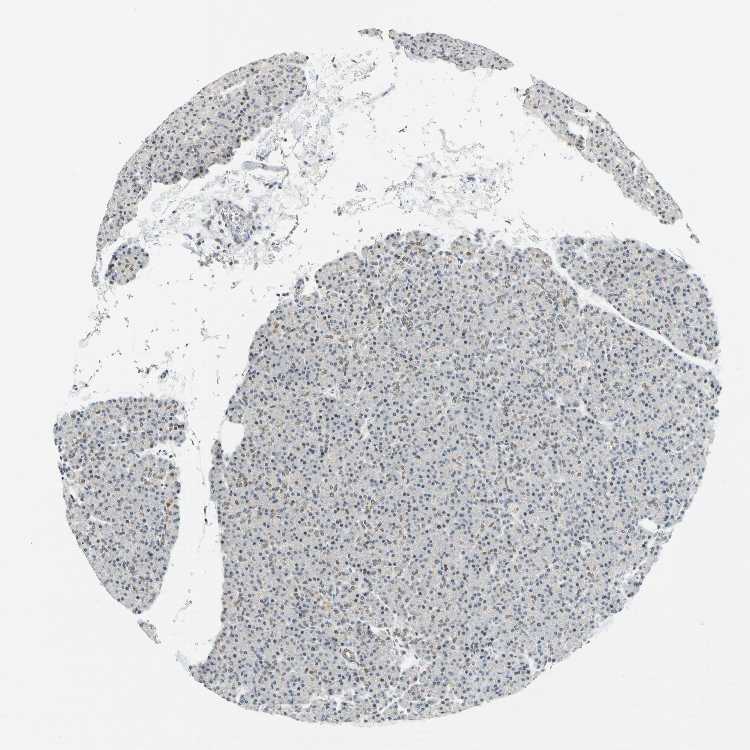

PANCREAS - Antibody stainingi

Antibody staining in the annotated cell types in the current human tissue is reported as not detected, low, medium, or high, based on conventional immunohistochemistry profiling in selected tissues. This score is based on the combination of the staining intensity and fraction of stained cells.

Each image is clickable and will lead to virtual microscopy that enables deeper exploration of all samples and also displays staining intensity scores, fraction scores and subcellular localization as well as patient and tissue information for each sample.

Antibody HPA006800Antibody HPA008781

Exocrine glandular cells MediumMedium

Pancreatic endocrine cells Not detectedLow